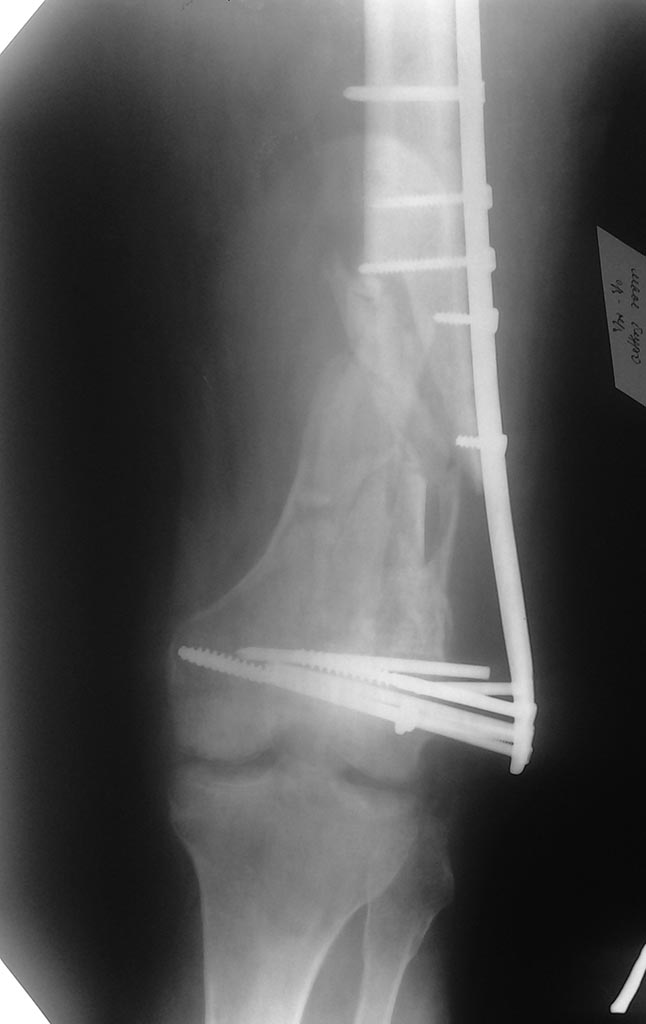

Уважаемые коллеги! Прошу помощи в выборе метода операции. Больному 64

года, пострадал в ДТП в декабре 2013 года в ДТП. Множественная травма:

сегментарный перелом правой локтевой кости,оскольчатый перелом левой

бедренной кости в нижней трети, перелом обеих лодыжек левой голени.

Операции МОС перелома костей предплечья пластинами, МИПО перелома бедра

пластиной, мос лодыжек. Через 4 мес на костылях оступился, произошла

полная нагрузка на ногу, одномоментно возникла деформация бедра. На

данный момент обсуждаются 2 варианта операции (с учетом предположительно

неудовлетворительного состояния губчатой ткани в мыщелках бедра:

1) удаление фиксаторов, ретроградно БИОС с костной аутопластикой зоны

перелома (Интерлок, дистальное блокирование 1 спиральным винтом 12 мм и

двумя 6 мм в разных плоскостях)

2) удаление фиксаторов, более длинная аналогичная пластина с угловой

стабильностью, наложенная по принципу "шинирования", в проксимальном

отделе фиксировать 4-мя винтами в значительном удалении от перелома, в

дистальном отделе расположить чуть ниже, костная аутопластика.Заранее

спасибо за конструктивную критику и советы.